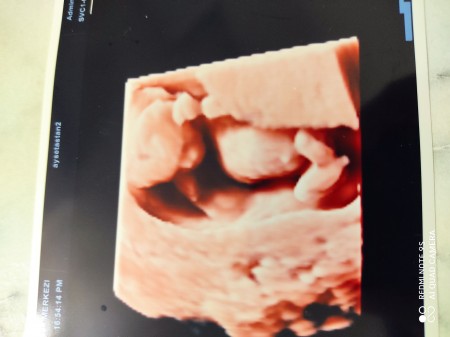

Kizlar cinsiyet tahmin 13+4 kendini göstermedi bağdaş kurdu elleriyle kaptti sizlerden tahmin aliyim

Gebelik haftası 13+4

Kız bu nasıl bı goruntu bulut falan sandim

Kizzz canim utandigina gore

Ultrason kalitesi çok kötü

Tahminim kız canım kıza benzettim